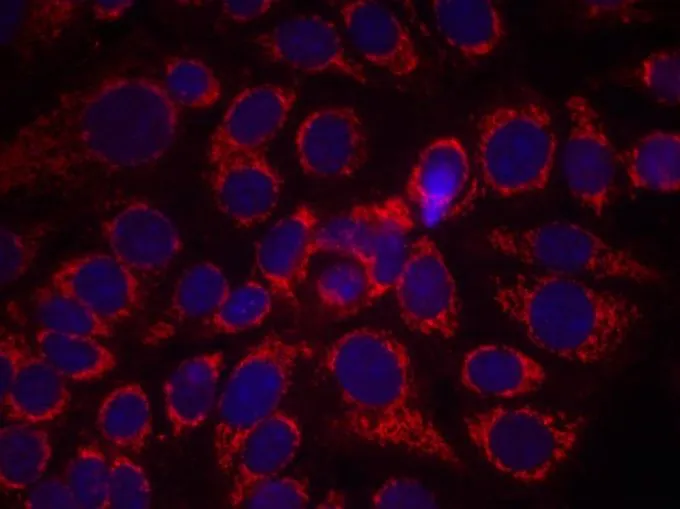

ICC/IF analysis of methanol-fixed MCF-7 cells using GTX50146 Her2 / ErbB2 (phospho Tyr1248) antibody.